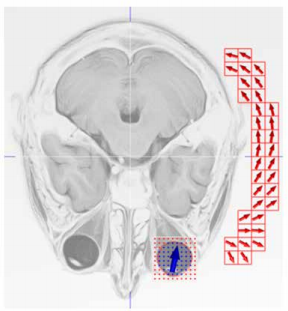

Our article "Simulationsbasierte Optimierung eines Magnetfeldapplikators für Arzneitransport (Optimization of Magnetic Field-based Applicator for Drug Delivery by Means of Simulations)" has appeared in the April issue of the Innovation & Markt journal published by Verband Innovativer Unternehmen e.V. (Germany-wide Association of Innovative Companies). This study has been done in frames of the project "Demonstration der magnetischen Wirkstoffverabreichung zum Auge (Proof of Concept Demonstration of Drug Delivery to the Eye)" lead by Prof. Silvio Dutz from TU Ilmenau and financed by the Thüringer Aufbaubank (TAB). 07.05.2021